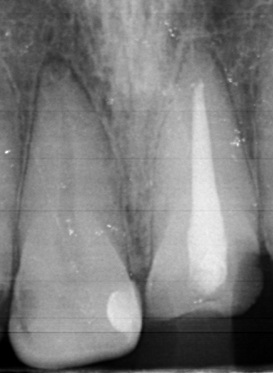

2323.jpg 238Кб, 1412x2047

1412x2047

Аноны, добрый вечер.